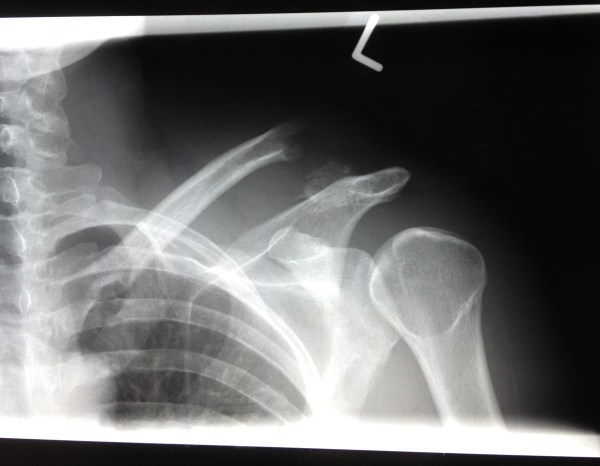

Dr. Moro (highly regarded surgeon I was lucky to get hooked-up with) went over my X-rays with me and told me about the different options. Seeing that there was a 26mm gap between the two parts of my clavicle, he suggested that a plate be inserted to ensure the bone joins again. The main part of my clavicle was much higher than usual because I ripped the ligaments that hold it in place. Luckily a bed was available later that afternoon and I was able to go under the knife that evening.